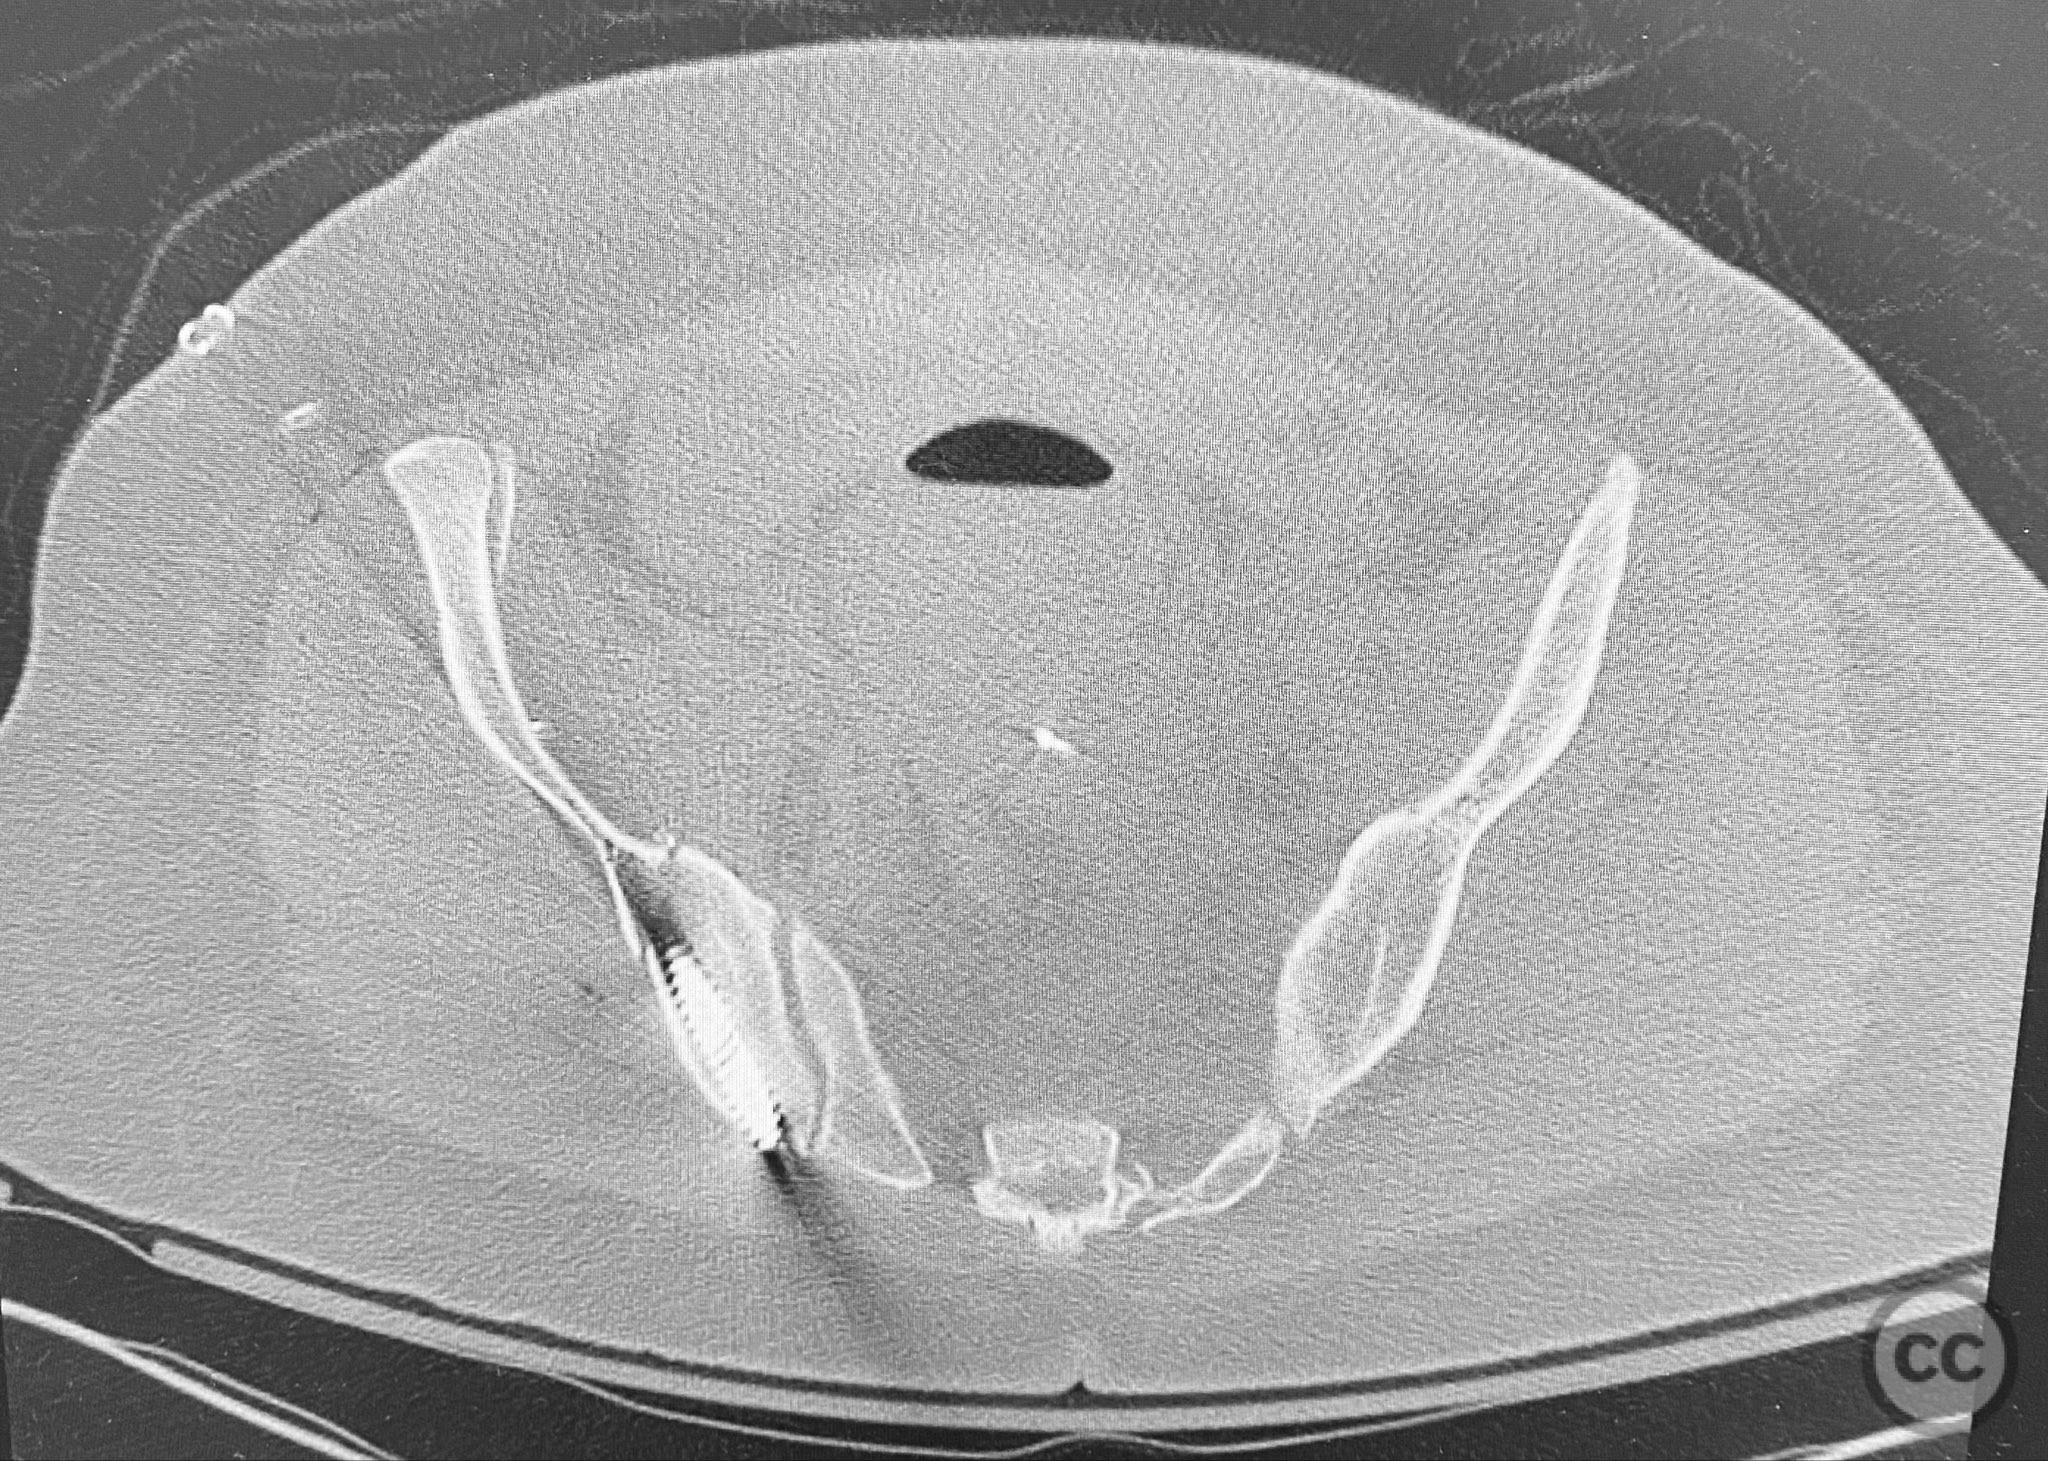

Clinical and radiological findings:  The patient presented following trauma with an unusual, significantly displaced right iliac fracture, accompanied by left-sided sacral and parasymphyseal ramus fractures. Initial AP pelvic radiography demonstrated the complex injury pattern. CT imaging provided detailed characterization of the iliac and sacral fractures, including assessment of displacement, bone quality, soft tissue status, and overall body habitus. No neurovascular compromise was reported. AO/OTA classification: Right iliac fracture 61B2.3 (partial unstable, lateral compression injury), left sacral fracture Denis zone I, left parasymphyseal ramus fracture.